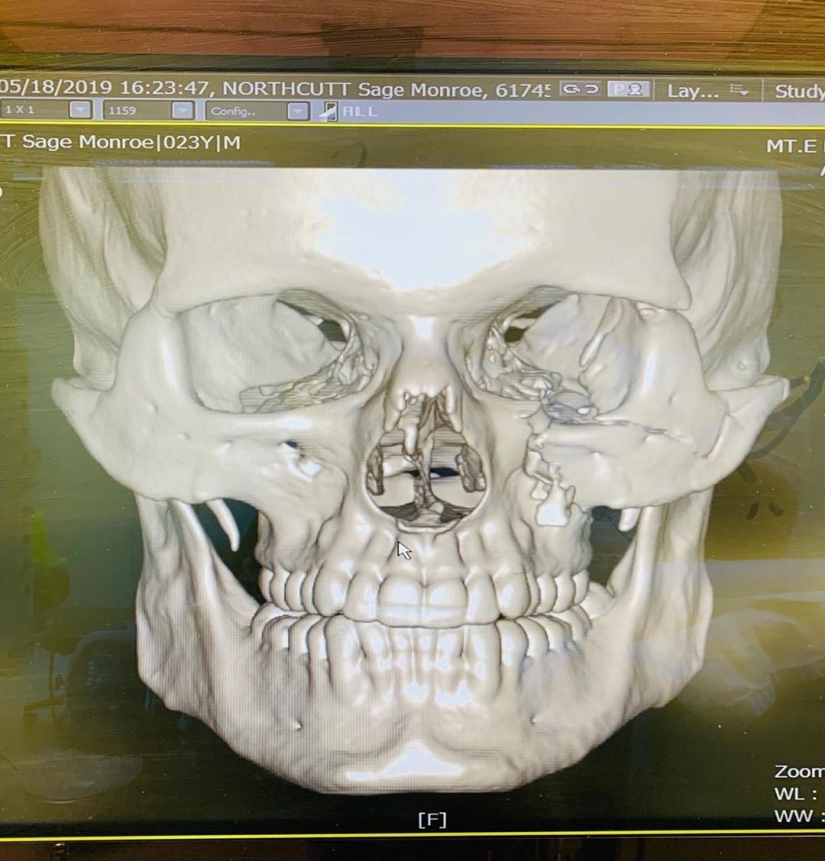

At the hospital, doctors X-rayed Northcutt's head, and it turned out that the skull of the 23-year-old American is more like the skull of a century-old mummy. With photos, as well as detailed information about the current state of the fighter, you can find in our material.

The guy was taken to the hospital, where he underwent a 9-hour operation. In total, Northcutt had 8 fractures.

This is how the skull of the fighter looked on the X-ray. Many netizens noticed that he — with all the cracks and humps — looks more like the skull of a hundred-year-old mummy, not a 23-year-old guy.